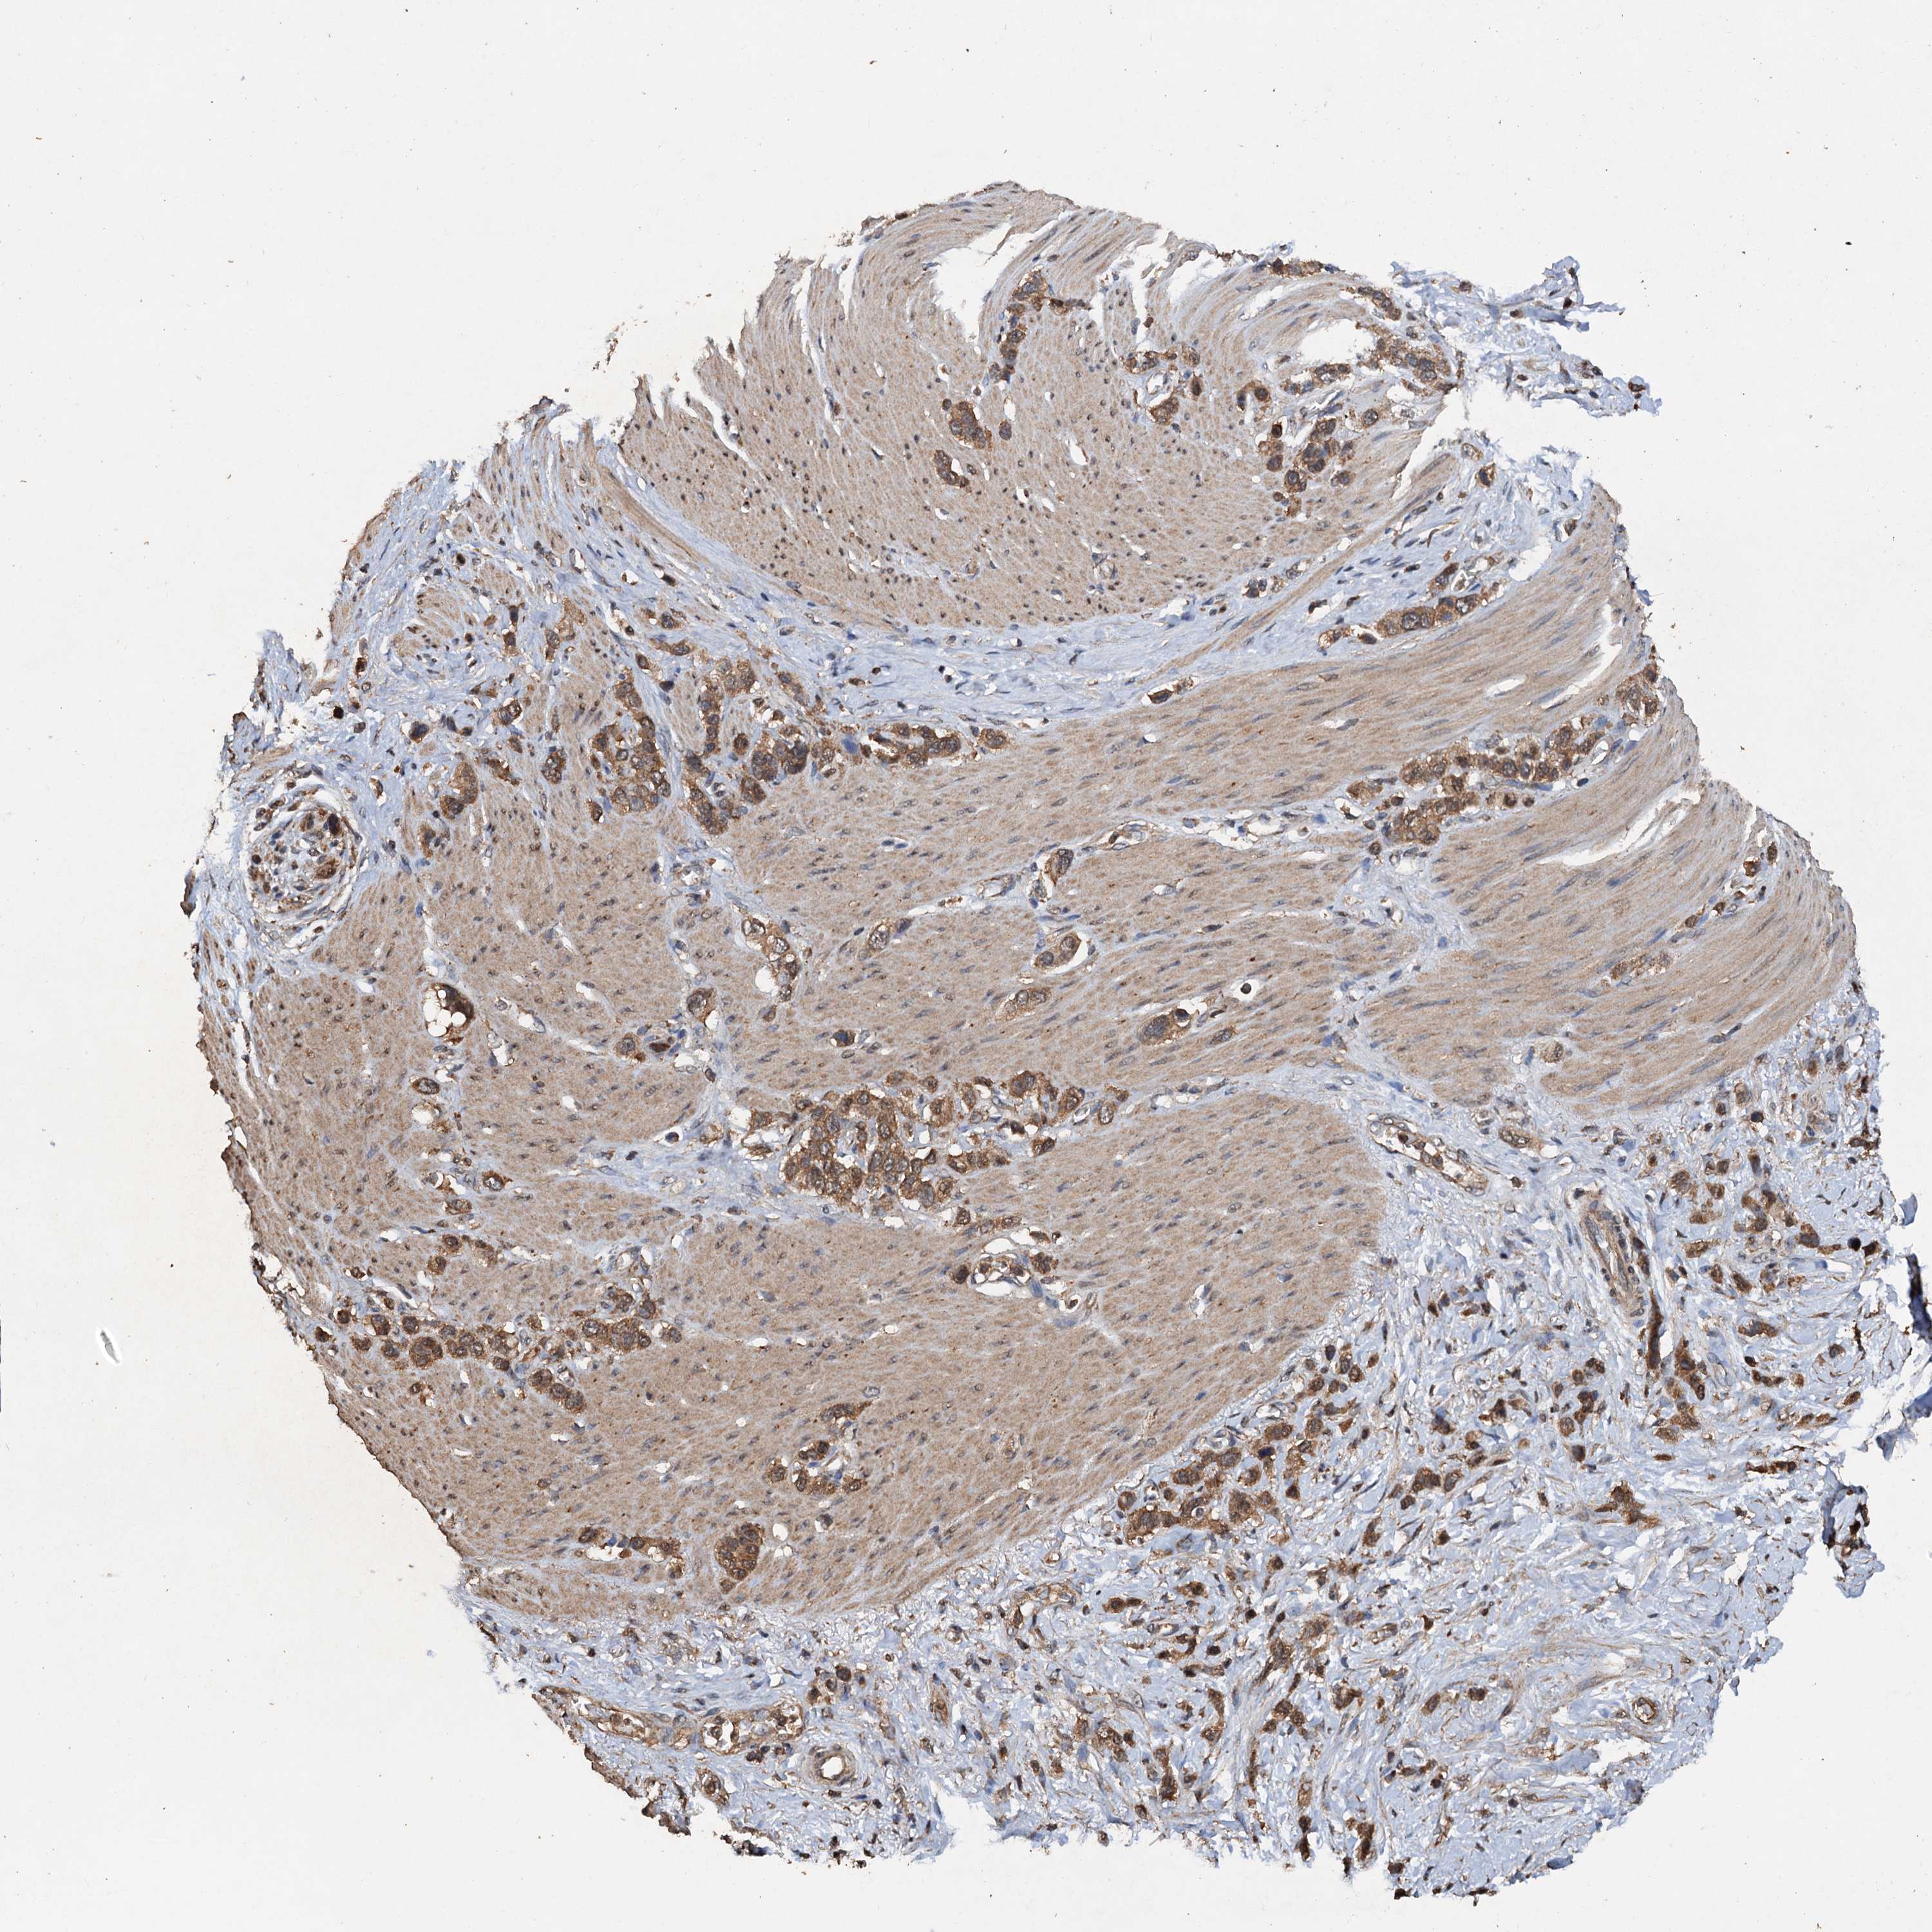

STOMACH CANCER - Protein expressioni

A mouse-over function shows sample information and annotation data. Click on an image to view it in a full screen mode. Samples can be filtered based on level of antibody staining by selecting one or several of the following categories: high, medium, low and not detected. The assay and annotation is described here.

Antibody stainingi

Antibody staining in the annotated cell types in the current human tissue is reported as not detected, low, medium, or high, based on conventional immunohistochemistry profiling in selected tissues. This score is based on the combination of the staining intensity and fraction of stained cells.

Each image is clickable and will lead to virtual microscopy that enables deeper exploration of all samples and also displays staining intensity scores, fraction scores and subcellular localization as well as patient and tissue information for each sample.

Antibody HPA040512

Antibody HPA044220

Staining

High

Medium

Low

Not detected

Intensity

Strong

Moderate

Weak

Negative

Quantity

>75%

75%-25%

<25%

None

Location

Nuclear

Cytoplasmic/membranous

Cytoplasmic/membranous,nuclear

Adenocarcinoma, NOS

Adenocarcinoma, High grade